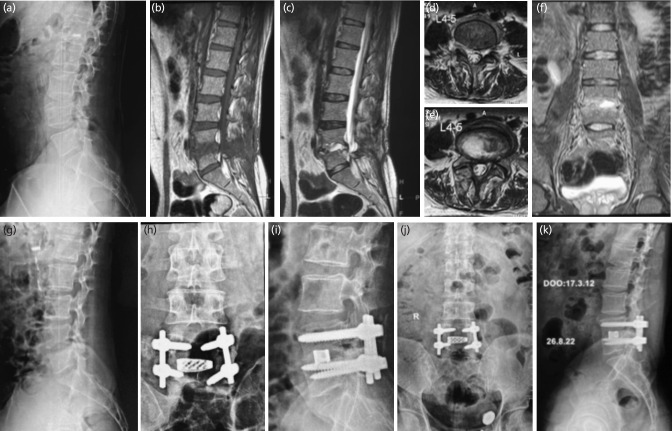

Material and methods: Retrospective analysis of patients operated by transforaminal lumbar interbody fusion (TLIF) in POS was done. Confirmed clinico-radiological diagnosed POS cases, not responding within three to four weeks were included. Normalisation of CRP and radiological stable reconstruction was assessed for objective clearance of POS and bony union.

Results: Ninety-five patients were included in the study with minimum follow-up period of two years. The mean age was 51.63±13.63 years. There were organisms cultured in 55 patients (57.89%). The ODI improvement of the patients was noted to improve from 88.71±5.3 to 20.80±9.7 (8 weeks) and was incremental at 2 years follow-up (10.12±6.41) and maintained further at final follow-up at 9±4.3. Bony union achieved in all with stable reconstruction. The resumption of activities of daily living (ADL) was quick (15.90±8.20 days) and job (3.67±1.31 months) was achieved in all the patients. In poor outcomes, two patients didn't respond, and one patient died due to uncontrolled infection.